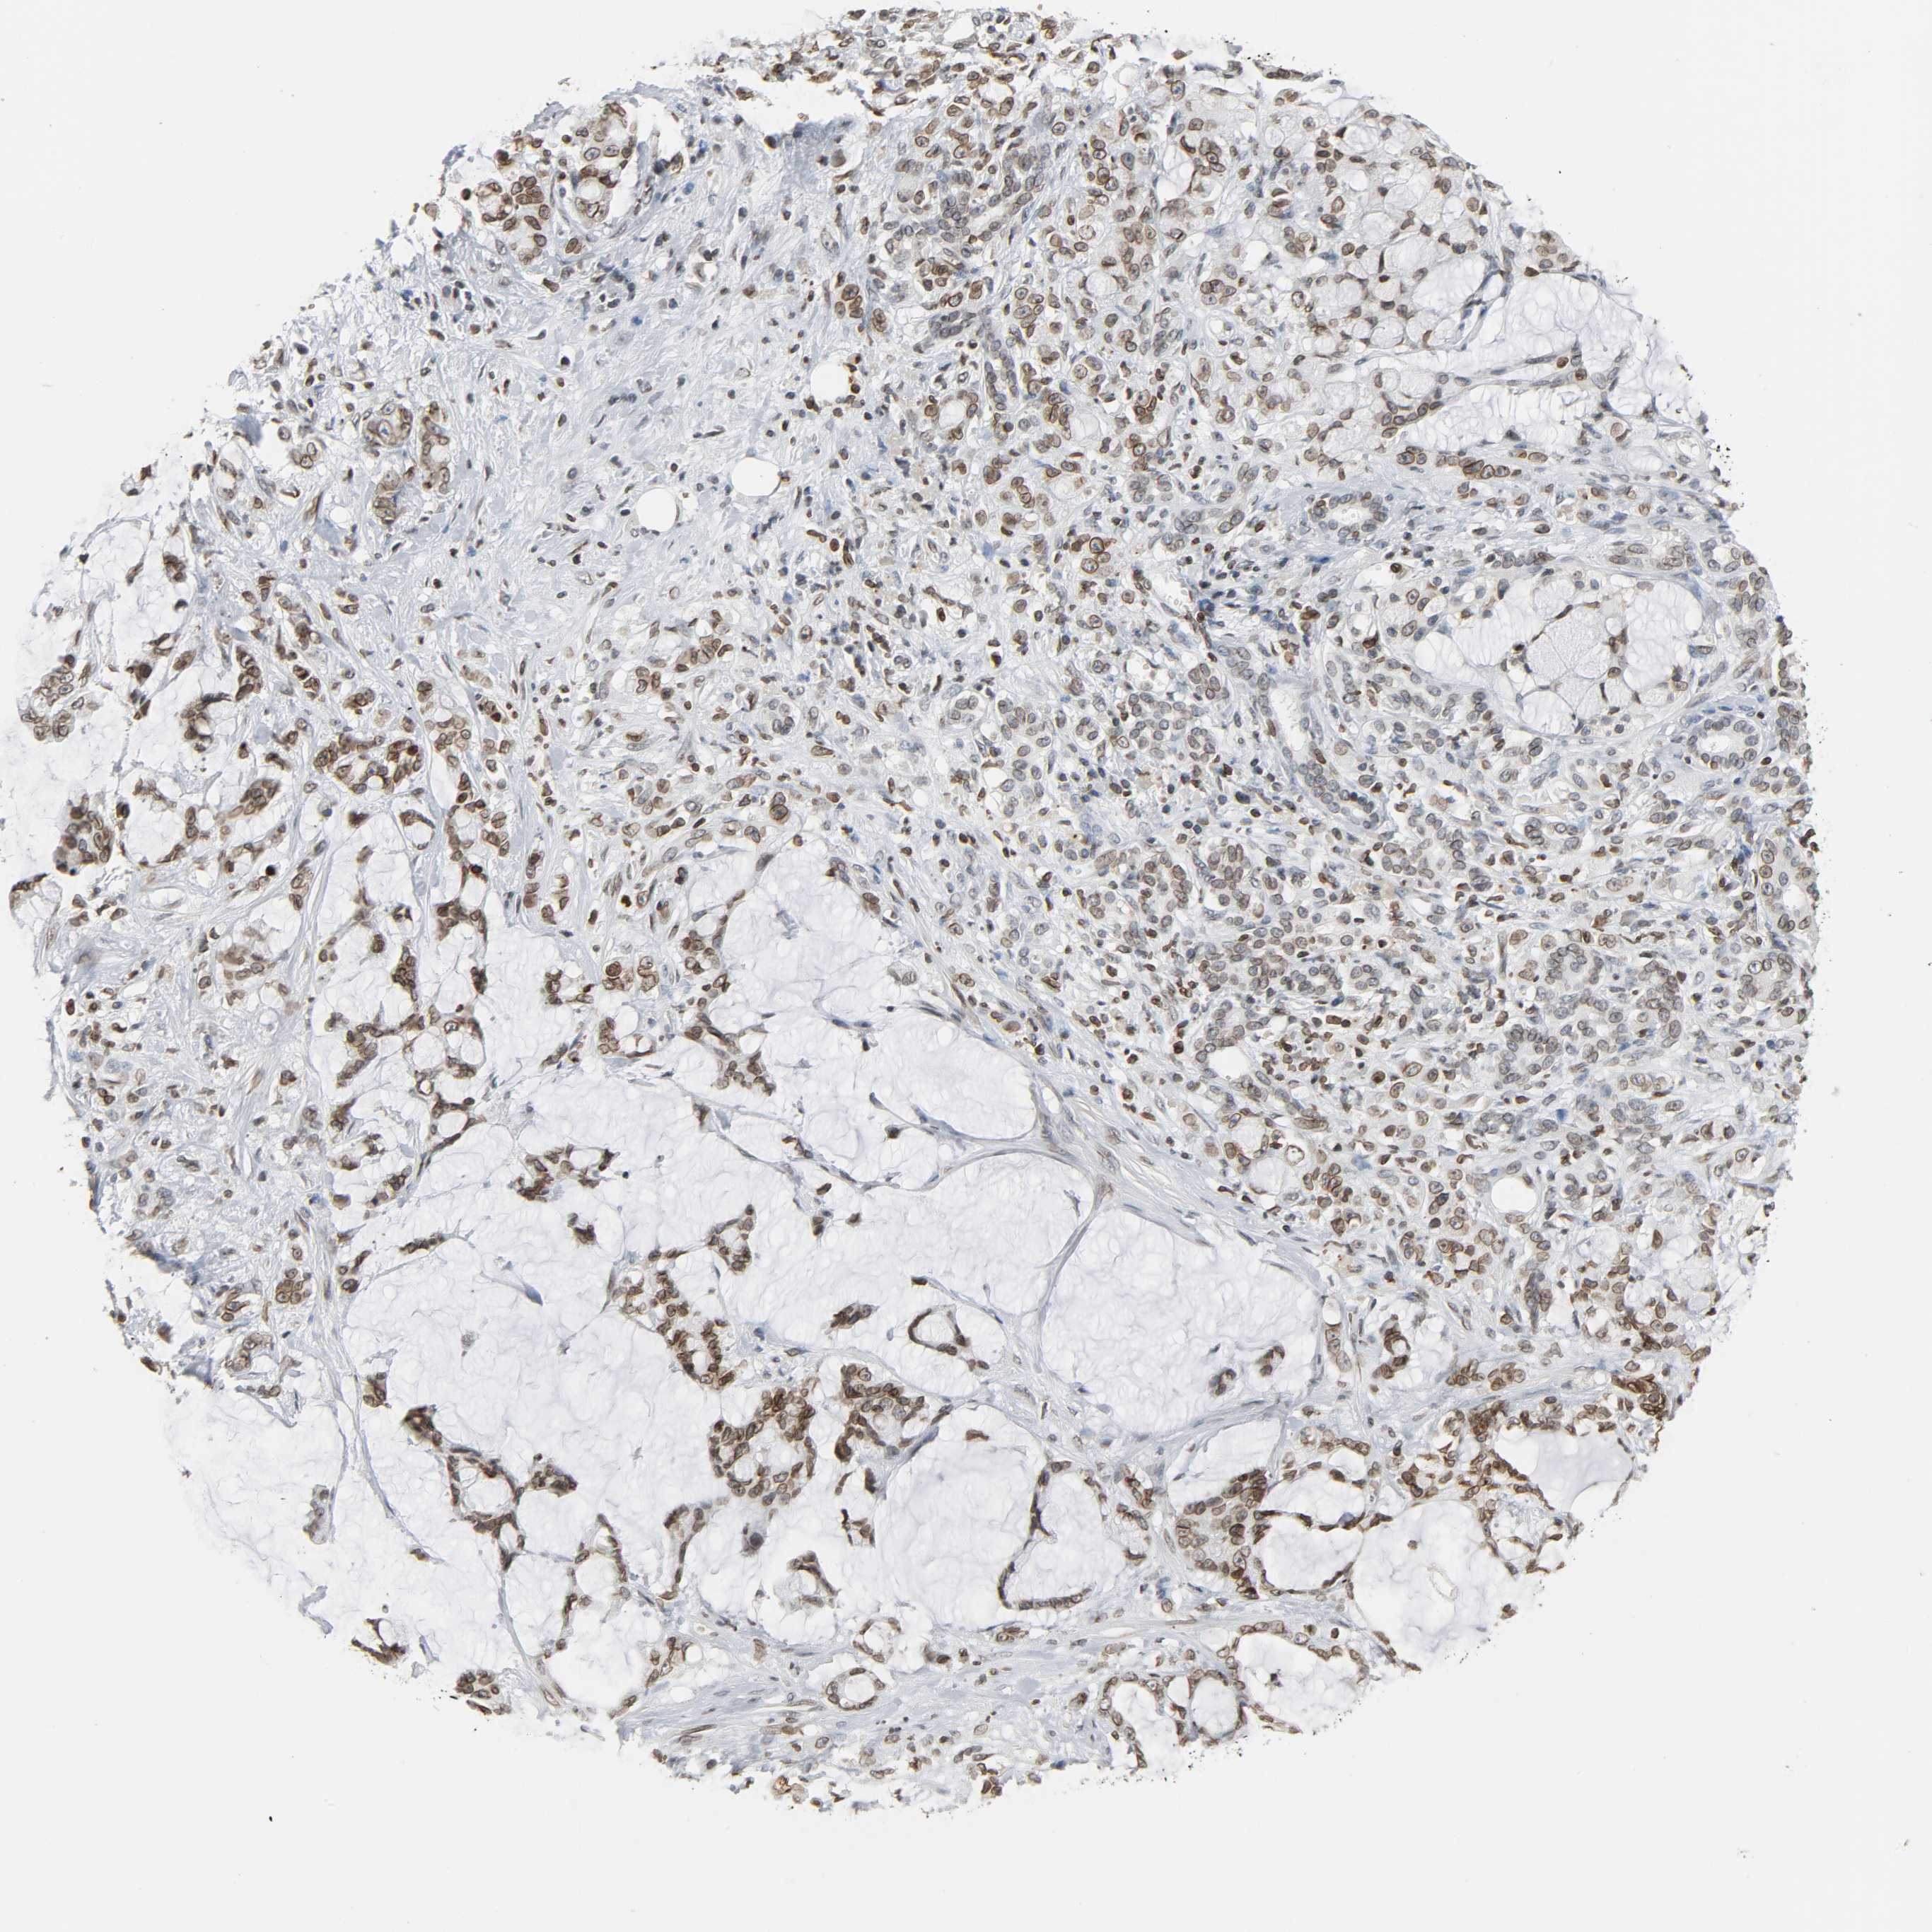

PANCREATIC CANCER - Protein expressioni

A mouse-over function shows sample information and annotation data. Click on an image to view it in a full screen mode. Samples can be filtered based on level of antibody staining by selecting one or several of the following categories: high, medium, low and not detected. The assay and annotation is described here.

Note that samples used for immunohistochemistry by the Human Protein Atlas do not correspond to samples in the TCGA dataset.

Antibody stainingi

Antibody staining in the annotated cell types in the current human tissue is reported as not detected, low, medium, or high, based on conventional immunohistochemistry profiling in selected tissues. This score is based on the combination of the staining intensity and fraction of stained cells.

Each image is clickable and will lead to virtual microscopy that enables deeper exploration of all samples and also displays staining intensity scores, fraction scores and subcellular localization as well as patient and tissue information for each sample.

Antibody HPA004246

Antibody CAB018641

Staining

High

Medium

Low

Not detected

Intensity

Strong

Moderate

Weak

Negative

Quantity

>75%

75%-25%

<25%

None

Location

Nuclear

Cytoplasmic/membranous

Cytoplasmic/membranous,nuclear

Adenocarcinoma, NOS

Adenocarcinoma, metastatic, NOS